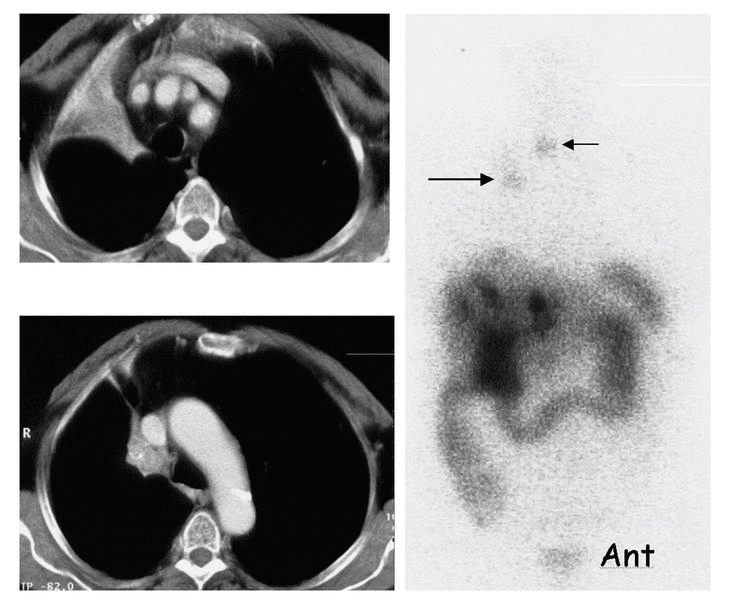

Fig. 1. --Tumor carcinoide bronquial parahiliar derecho. TC: Masa parahiliar superior derecha de 3 × 2 ×2 cm, en contacto con la pleura mediastínica, que produce atelectasia del lóbulo superior derecho. GRS: Expresión de receptores de SS por parte del tumor (flecha larga). Metástasis hepáticas múltiples, no detectadas en la TC, y metástasis en D-3 (flecha corta).